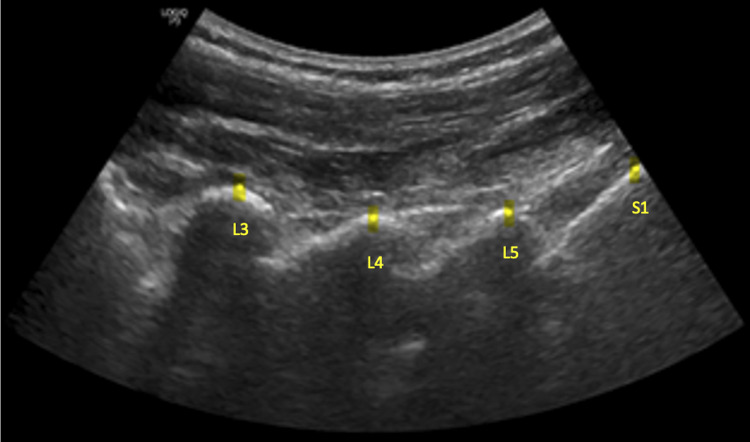

Methods: This study analyzed a convenience sample of generally healthy participants, aged 21 years and older, from both sexes and various ethnicities who reported no back pain. Participants were recruited through announcements and flyers posted around the Keiser university campus. Data was collected from June-August 2022. The participants were positioned prone on a specialized flexion distraction chiropractic table. Ultrasound imaging was performed to measure the spinous process distance from L3-S1 before the procedure, during flexion distraction utilizing standard Protocol I, and post-procedure. Ultrasound measurements were recorded by identifying the tips of the spinous processes and distances between L3-L4, L4-L5, and L5-S1, before, during, and after flexion distraction. Statistical analyses included paired t-tests to evaluate spinous process distances pre- and during Cox® Flexion distraction, independent t-tests for gender differences, and linear regression for body mass index (BMI) and age correlations with changes in separation distance.

Results: Thirty participants (16 male, 14 female) with a mean age of 32.5 years (Standard deviation [SD] 10.4), mean weight of 69.2 Kg (SD 11.8), mean height of 169.0 cm (SD 8.9), and BMI of 23.9 underwent Cox® Flexion Distraction Protocol I. Spinous process separation increased during treatment: L3-L4 (0.13 mm), L4-L5 (0.13 mm), and L5-S1 (0.16 mm). Paired ttests showed significant pre- and during-treatment changes (p < 0.001), with moderate correlations to BMI (R²=0.61) and age (R²=0.58). Gender differences did not reveal statistical differences in separation distances at all lumbar levels measured (p > 0.1).

Conclusion: Ultrasound imaging revealed significant separation of spinous processes at L3-L4, L4-L5, and L5-S1 during Cox® Flexion Distraction Protocol I. Statistical analyses showed separation correlated moderately with age and BMI that was unaffected by gender. Future studies should assess this technique's relevance in patients with low back pain.